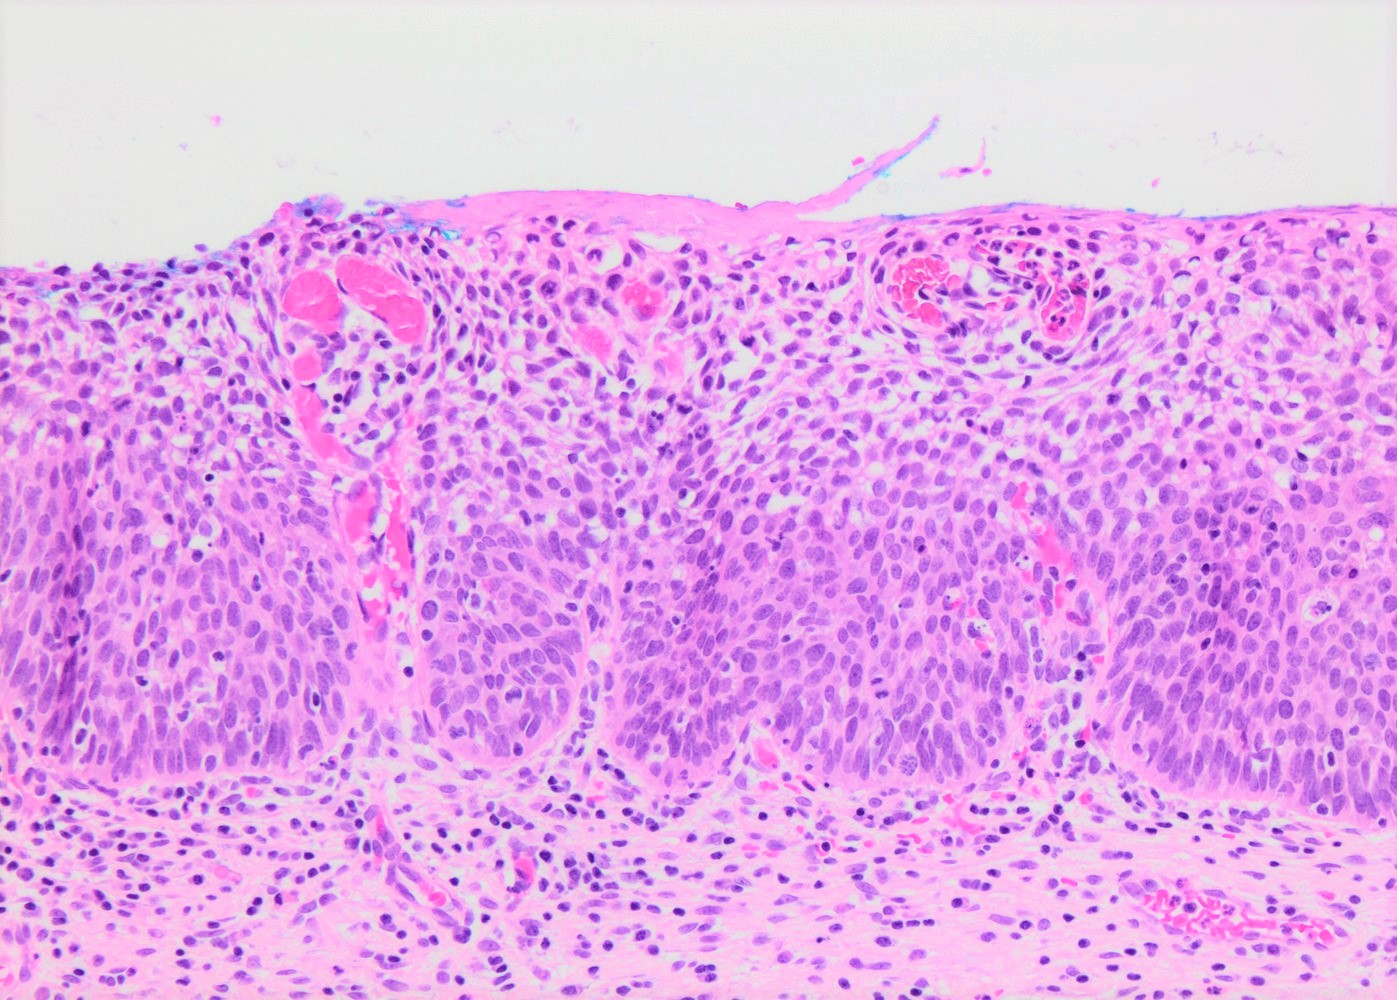

- Conventional / classic pattern: full thickness nuclear abnormalities (hyperchromasia, coarse chromatin, irregular nuclear contours and inconspicuous nucleoli), high N/C ratio in at least lower two - thirds of epithelium

- CIN II: cytoplasmic maturation in the upper third of mucosa

- CIN III: full thickness basal / parabasal type, no maturation difference across layers

- Increased mitotic activity with atypical mitoses

Microscopic (histologic) images

Contributed by Khaled J. Alkhateeb, M.B.B.S.